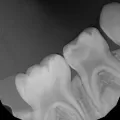

У моей дочери, возраст 1 год 6 месяцев, кариес эмали верхних шести зубиков, четыре передних резца и два жевательных. Кариес сейчас выглядит как желтые круглые бороздки на зубках. Были у детского стоматолога - сказала ставить пломбы под наркозом. Очень не хочу лечить зубки под наркозом, так как сомневаюсь в безопасности самого наркоза.

Есть ли способ отсрочить пломбирование хотя бы до возраста, когда можно применить седацию или "уговорить" ребенка лечить зубы? Может помочь фторирование?